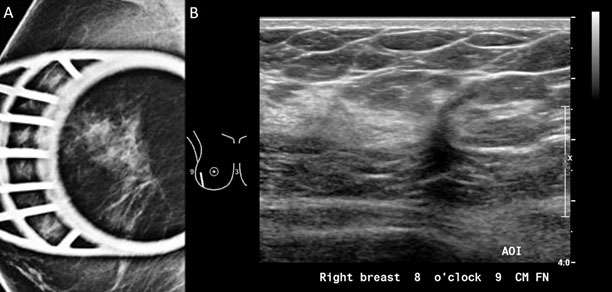

5. Spiculated: the margin is characterized by lines radiating from the mass. Use of this descriptor usually implies a suspicious finding (Figure 1A, Figure 6A).

Mammography: Masses Figure 6

Figure 6: A) Spiculated mass was visualized in the right breast with spot compression view on mammogram. B) Sonographic evaluation of the right breast was performed in the region of the mammographic finding. At the 8:00 position 9 cm from the nipple, there is an irregular hypoechoic solid mass with indistinct margins oriented antiparallel to the chest wall demonstrating posterior shadowing, BI-RADS Category: 4C suspicious finding. Pathology confirmed invasive ductal carcinoma, Grade 1.